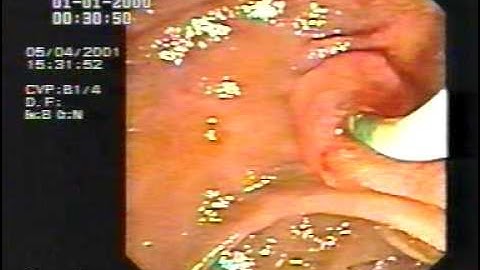

cholangioscopy via sphinctertome